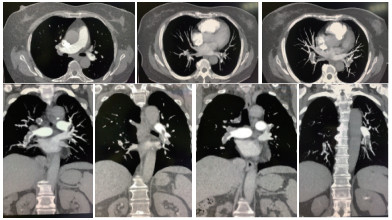

这是一例64岁的女性患者, 主因“胸闷、憋气4年,加重2周”入院。4年前患者因“活动后胸闷、憋气”外院行肺通气灌注扫描提示双肺多发PTE(累计4个肺段及1个亚肺段),诊断“急性PTE”,当时未行肺动脉增强CT(computed tomography pulmonary angiogram,CTPA)检查CTPA检查)。住院抗凝治疗,症状好转出院。院外长期口服华法林5.25 mg,睡前口服,最初3年规律监测凝血指标,基本达标(INR 2~3)。患者初次发病没有明显诱因,对坚持使用抗凝药物具体原因不清楚,4年间活动耐力基本恢复发病之前水平。近1年自行调整华法林剂量于3~5.25 mg/d,间断服药(间隔时间2~3 d不等)。2周前再次出现胸闷、憋气症状,伴轻度胸痛(与呼吸相关),无黑矇、头晕、晕厥、咯血等。凭借主观感觉恢复华法林剂量(5.25 mg/d),症状持续不缓解就诊于本院急诊。入院前连续两次凝血五项:PT 21.9~25.2 s,APTT 39.0~38.7 s,INR 1.88~2.16,D-Dimer 918~1230 ng/mL;CTPA提示“多发肺栓塞,累及双侧肺动脉主干及其分支”(图 1-7所示),心电图提示:窦性心动过缓(图 8所示)。为进一步诊治收入本科。

2.1 是否存在CTEPH的临床征象?本例有明确的PTE基础疾病及不正规治疗史,需要与CTEPH鉴别。但是我们可以通过以下几点影像学表现否定CTEPH的可能性[5]:超声心动图既没有右心室流出道明显增宽,也没有显示三尖瓣反流;心电图没有明确的右心室负荷过重的表现;CTPA肺动脉横径小于主肺动脉横径(图 1),右心室的横径小于左心室(房室瓣水平,图 2)。除此之外,还需要帮助学生学会如何通过CTPA影像学征象判断急性和慢性PTE[6-8]:①急性:马鞍征、环征、轨道征、偏心性充盈缺损与血管壁之间的夹角呈锐角均提示新鲜血栓;闭塞血管管径大于相邻同级别通畅的肺动脉管径。②慢性:偏心性充盈缺损边缘光滑,与血管壁之间的夹角呈钝角多见于慢性血栓;闭赛血管管径变细,管壁偏心增厚,可见钙化,管腔明显小于同级别通畅的肺动脉。